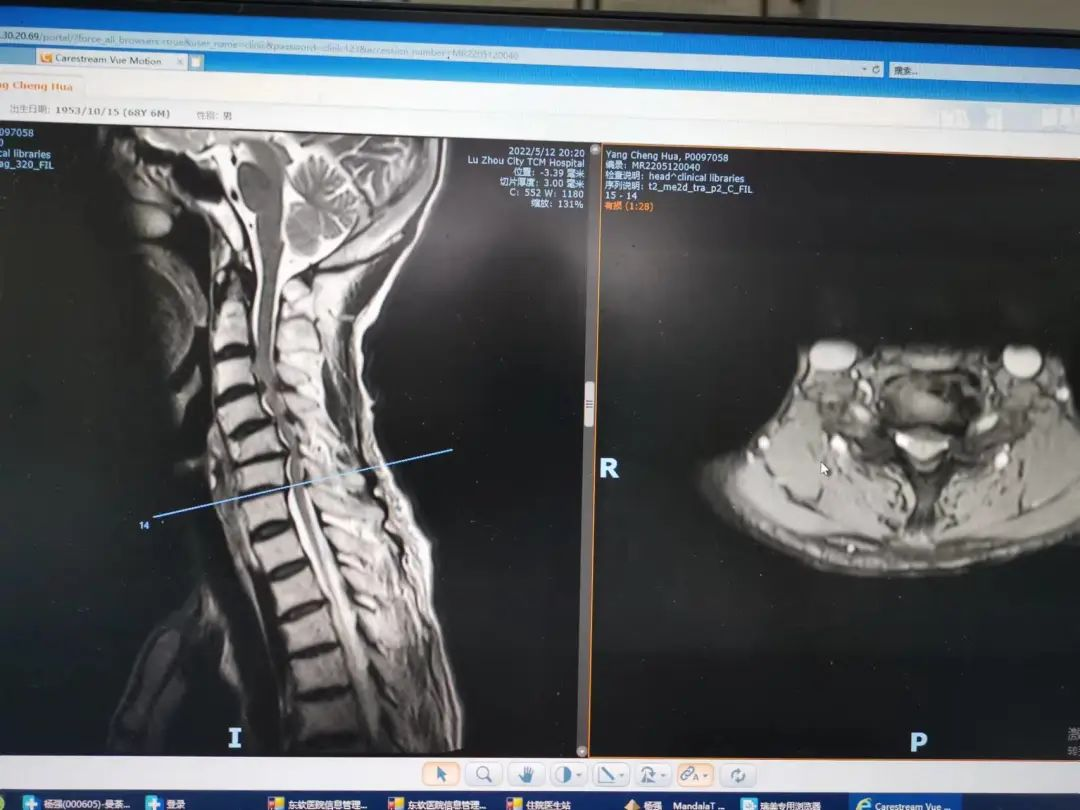

杨先生腰椎管狭窄症拍片

杨先生脊髓性颈椎病拍片

原来,杨先生无明显诱因的出现颈肩部、腰部疼痛,在当地医院住院治疗后症状稍缓解,随后疼痛症状又加重,并反复发作。近日,杨先生状况已是下地行走困难,还伴四肢疼痛、麻木、无力等,为求进一步治疗,杨先生来到泸州市中医医院就诊。经检查,杨先生是患了脊髓性颈椎病加腰椎管狭窄症

脊髓型颈椎病是由于颈椎退变导致椎间盘突出,骨熬增生,后纵韧带肥厚等压迫脊髓或压迫供应脊髓的而管,从而出现颈脊髓损害的颈椎疾病,其主要症状包括四肢感觉、运动、以及大小便功能障碍等,此病好发于50岁左右中老年人,男性居多,保守治疗效果差,常需要手术治疗。